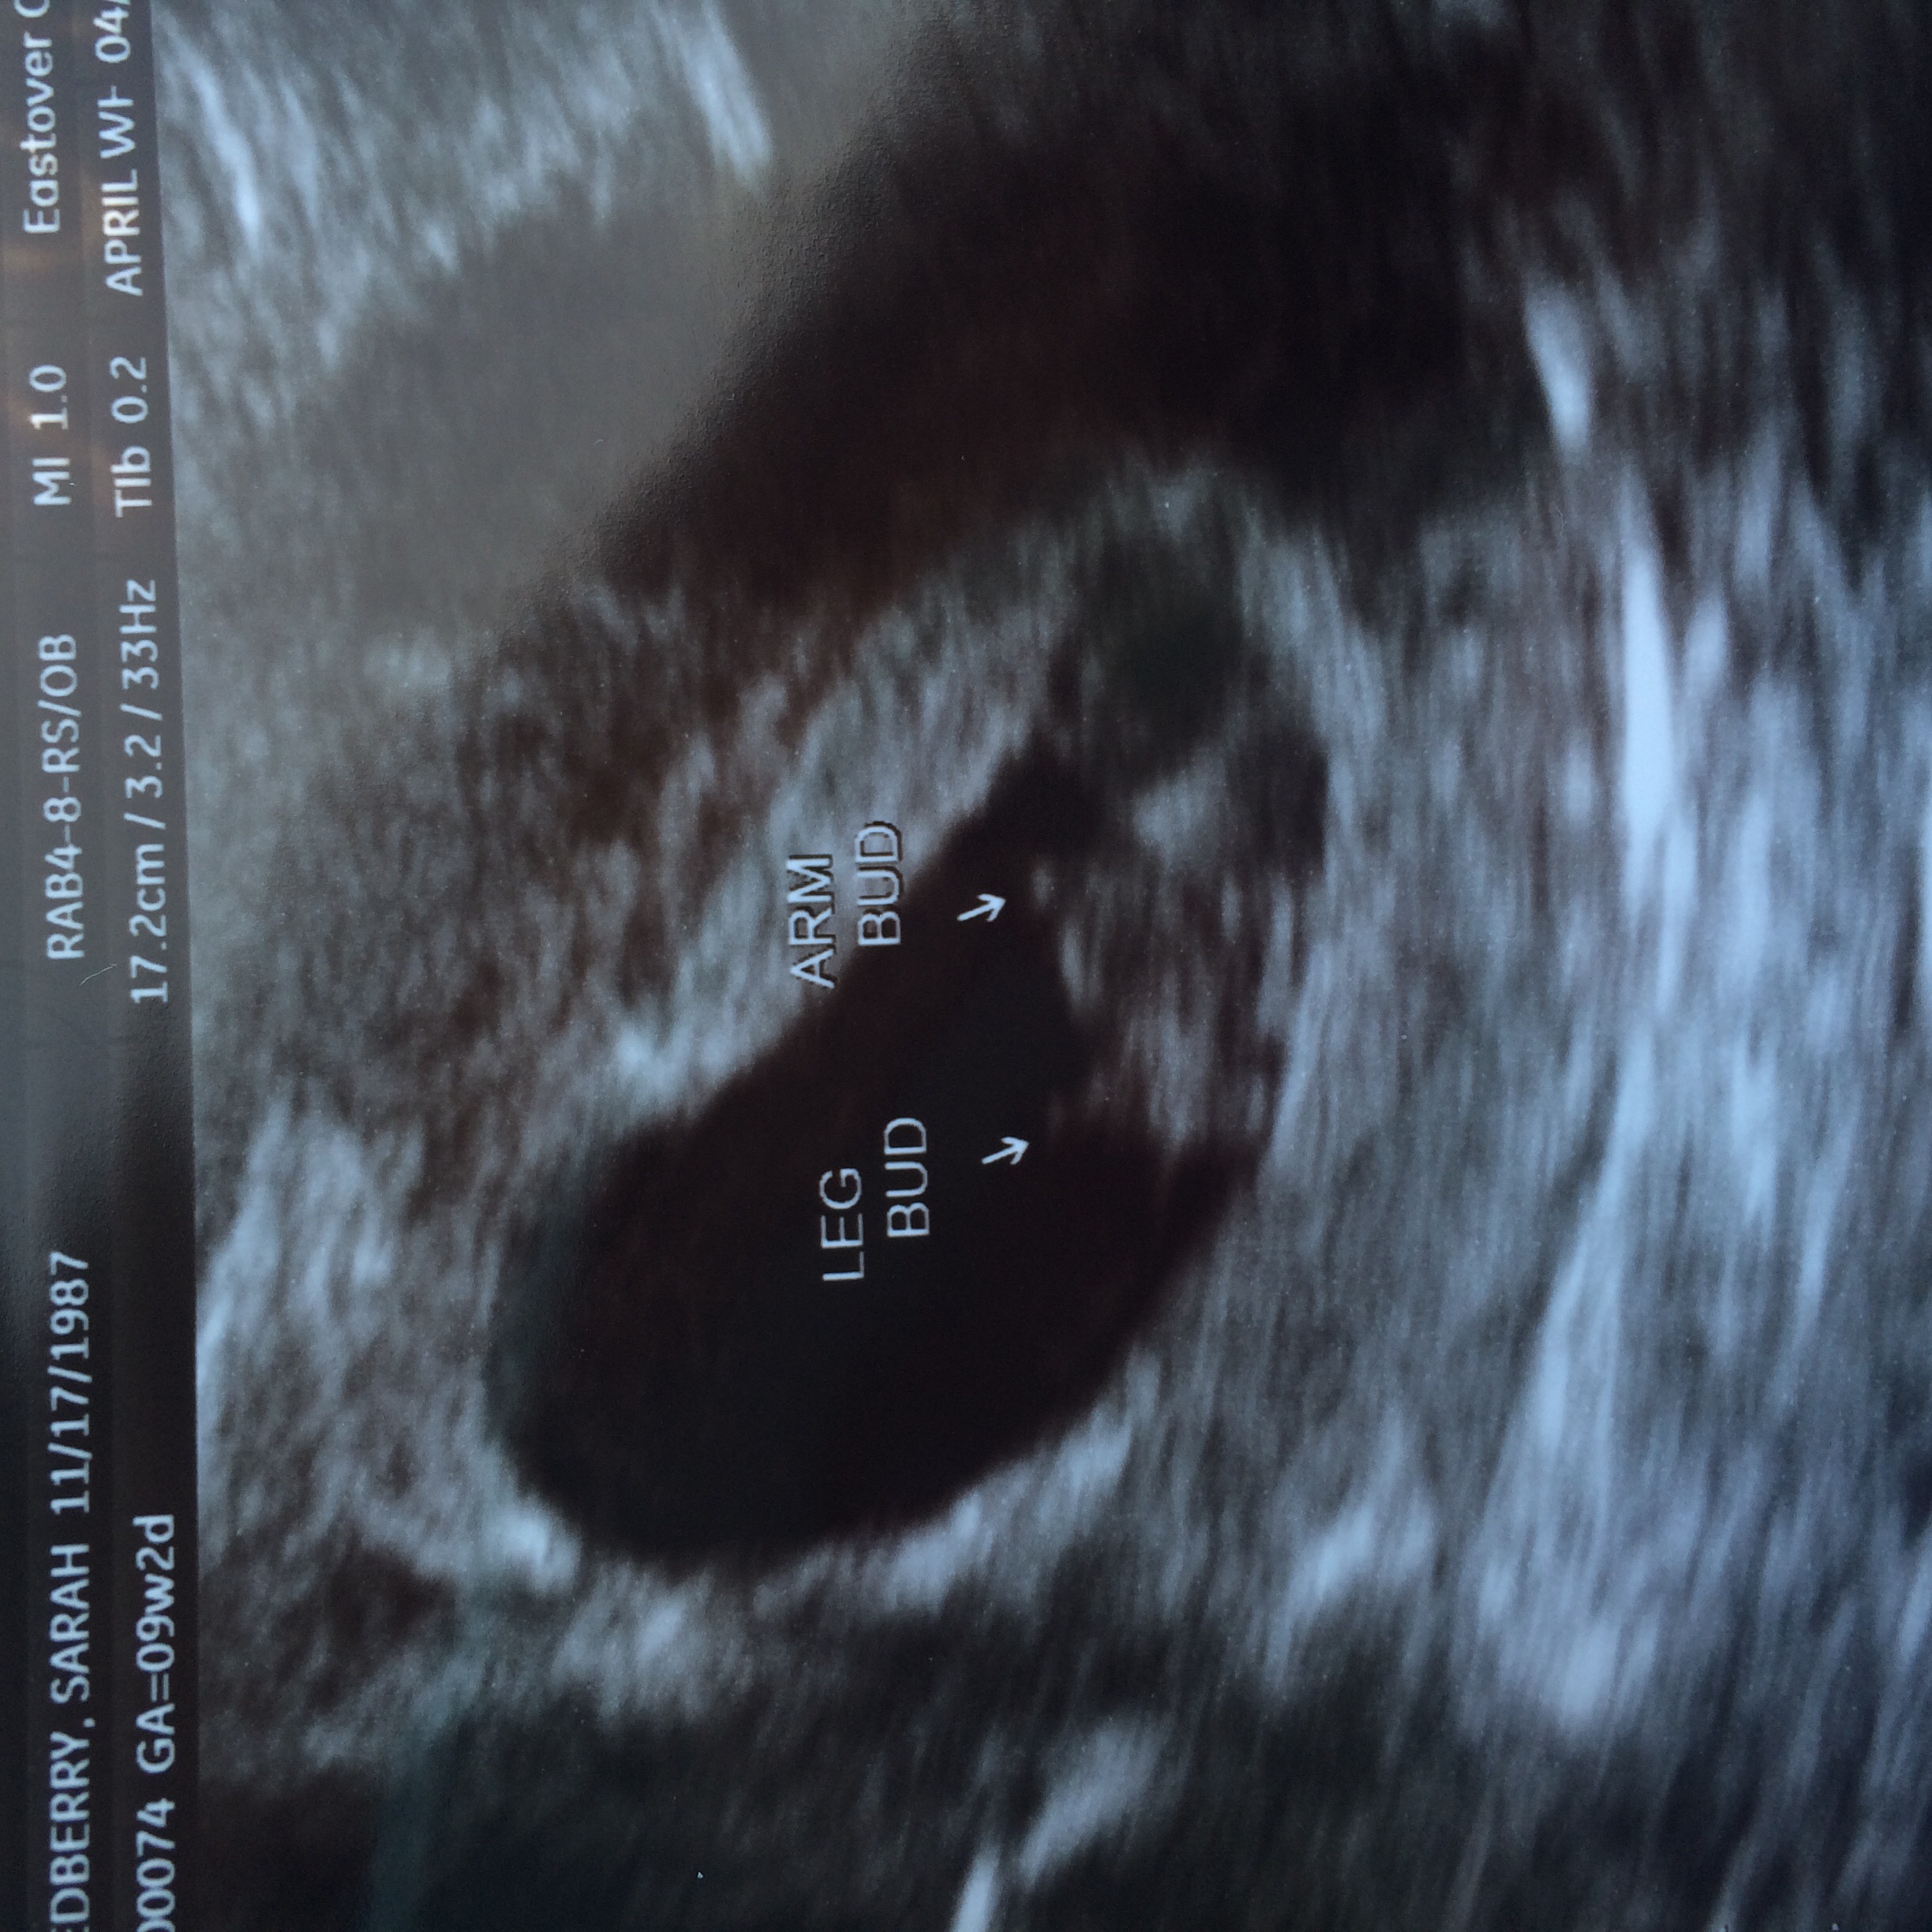

this was 7w1d I am 8w now.  I ran around waving it and telling people, "look!  Look what's in my uterus because I had sex!"  Toby said I was weird and needed to tone it down to "I am pregnant, would you like to see the u/s?" lmao  I word things oddly.